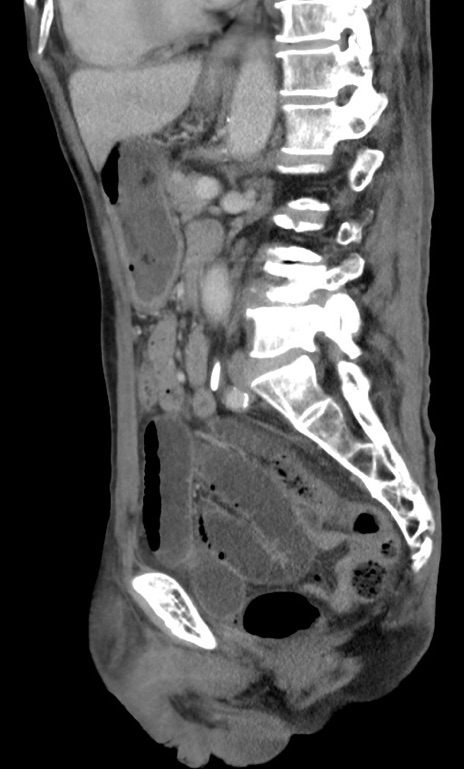

症例3(矢状断像)

【症例】 70歳代男性

【主訴】右鼠径部腫瘤、疼痛

【現病歴】本日朝より上記主訴あり、受診。

【既往歴】膀胱癌にて膀胱全摘、両側尿管皮膚瘻

【データ】WBC 5600、CRP 0.56